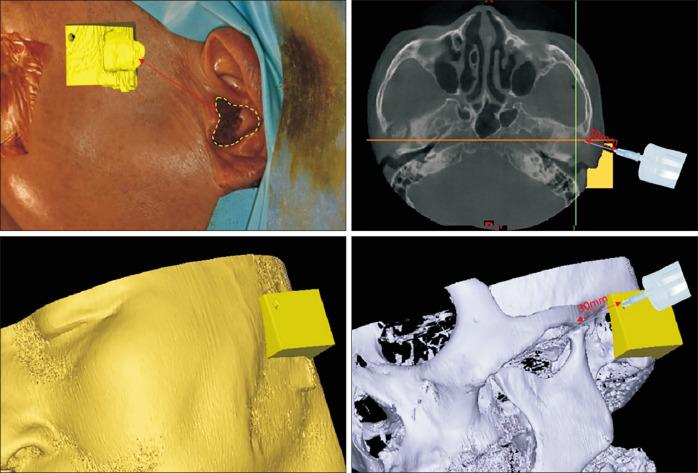

: This study aims to evaluate the accuracy and effectiveness of temporomandibular joint (TMJ) arthrocentesis using the three-dimensional (3D)-printed TMJ injection guide in cases of hemarthrosis caused by condyle fractures.

MATERIALS AND METHODS

: A retrospective chart review was conducted for patients treated with the customized TMJ arthrocentesis guide to address hemarthrosis. Inclusion criteria included adults older than 18 years with condylar fractures not indicated for open reduction and internal fixation. The guide was fabricated using computed tomography or cone-beam computed tomography scans and 3D printing to control the degree and depth of the needle through the guide to aspirate hemarthrosis.

本研究旨在评估在髁突骨折引起关节积血的病例中,使用三维(3D)打印的颞下颌关节注射导向器进行颞下颌关节(TMJ)关节穿刺术的准确性和有效性。

材料与方法

对采用定制的TMJ关节穿刺导向器治疗关节积血的患者进行回顾性病历审查。纳入标准包括年龄大于18岁、髁突骨折不适合切开复位内固定的成年人。该导向器通过计算机断层扫描或锥形束计算机断层扫描以及3D打印制作,以控制通过导向器穿刺抽吸关节积血的针的角度和深度。